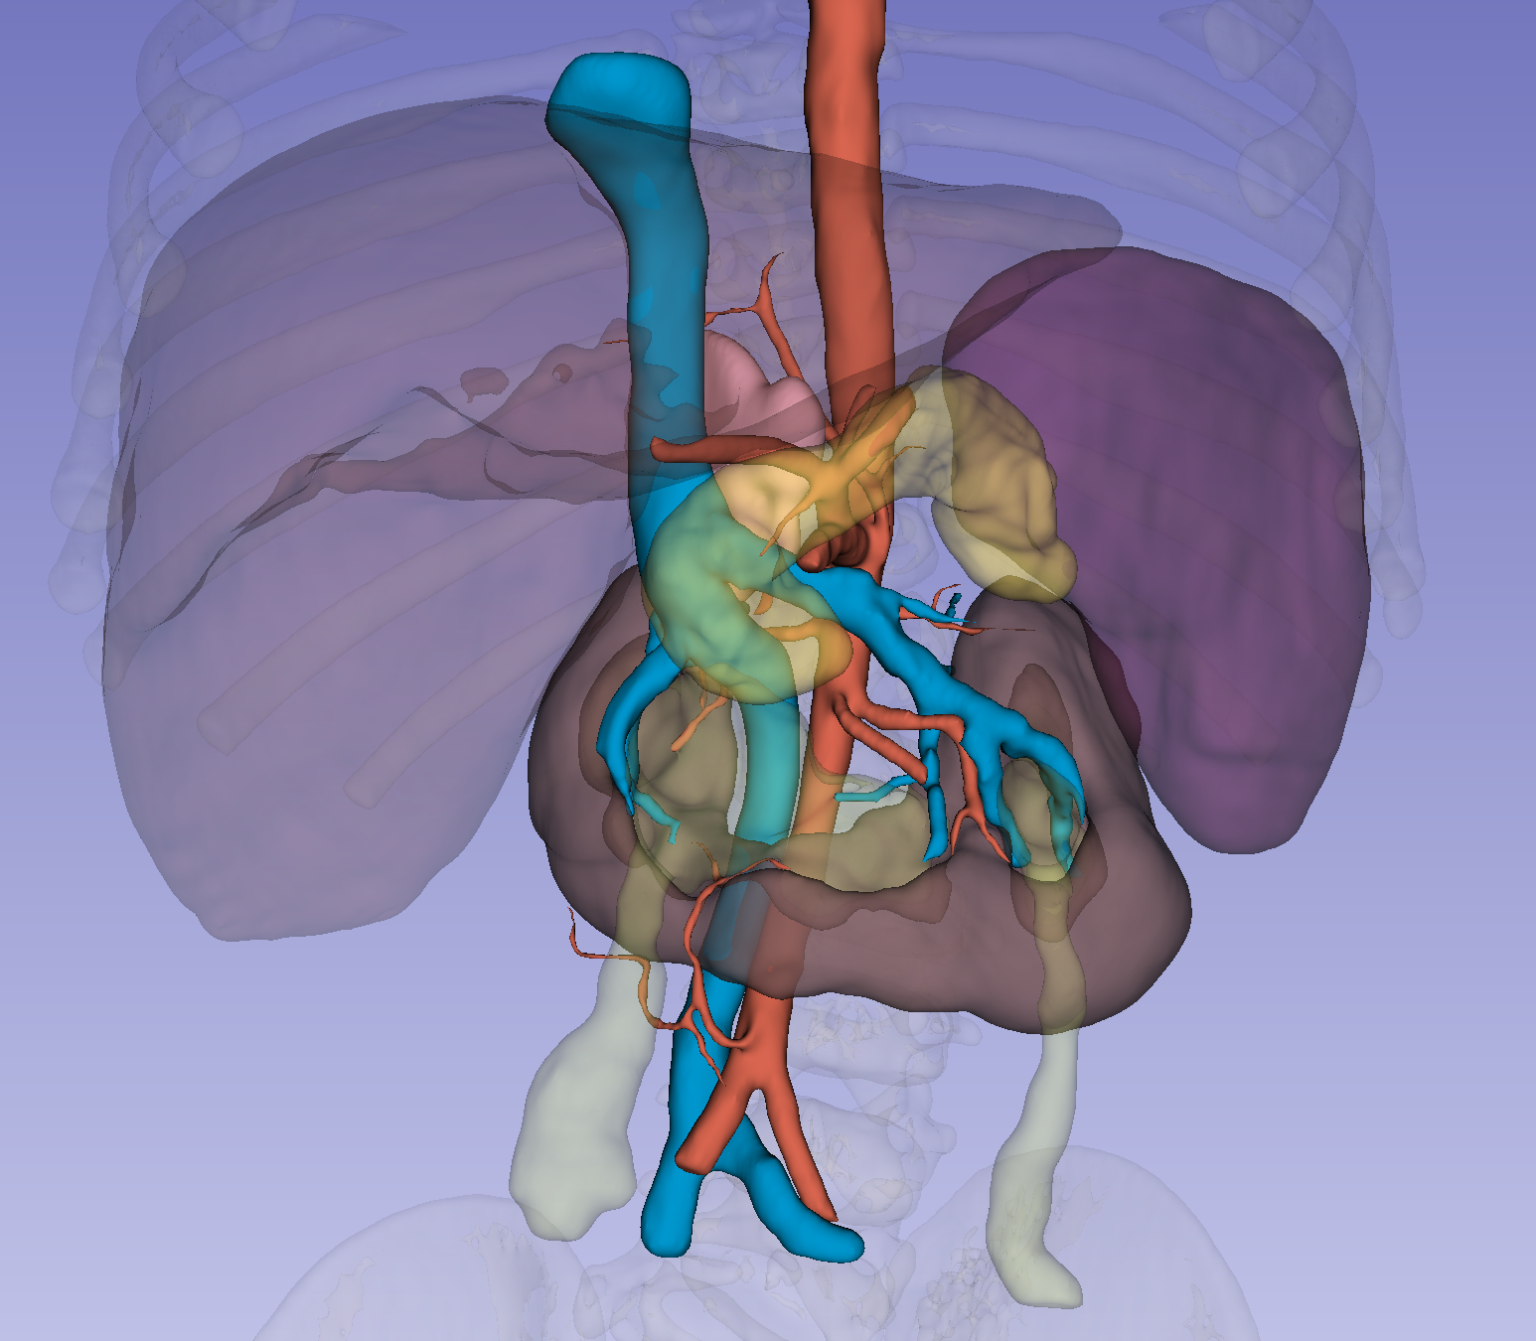

Virtual reality and ICG revolutionize pediatric neuroblastoma surgery, according to a new study from Printmed-3D and Buzzi Hospital.

We are pleased to announce the online publication in European Journal of Pediatric Surgery Reports of a new study resulting from a collaboration between Printmed

Virtual Reality, 3D printing of tissues and organs, and intelligent fluidics allow doctors to practice on models with characteristics identical to real ones, improving diagnosis,

Imagine that you know a person with a disease of the liver or another organ. Imagine that there is the possibility of creating in the